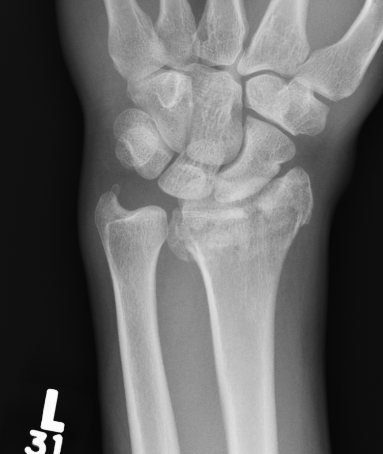

Distal Radius Angles

- radial volar tilt 11°

- radial inclination  22°

- radius is 11 mm longer than ulna

- ulna variance 2mm positive on average

Distal Radius NormalNormal Radial InclinationNormal Radial Length